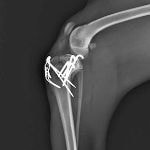

症例3:キルシュナーワイヤーのピンニングによる整復

ペルシャ猫 11ヶ月齢 雄

他院にて左大腿骨遠位の成長板骨折(salter-harrisⅠ型)が認められており、治療相談を目的として来院。当院にて、キルシュナーワイヤーを用いたピンニングにより骨折部位の整復を行いました。術後の経過は良好で、現在も経過観察中です。

術前レントゲン

術後レントゲン

機器

Arthrex社のターゲティングデバイスを用いてピンニングの位置を調整することで、確実な固定を行っています。当院ではこの手術器具以外にも、人の手術にも使用される様々な器具を導入し、手術精度を高め、また医療メーカーと新しい器具の開発、試作にも取り組んでおります。